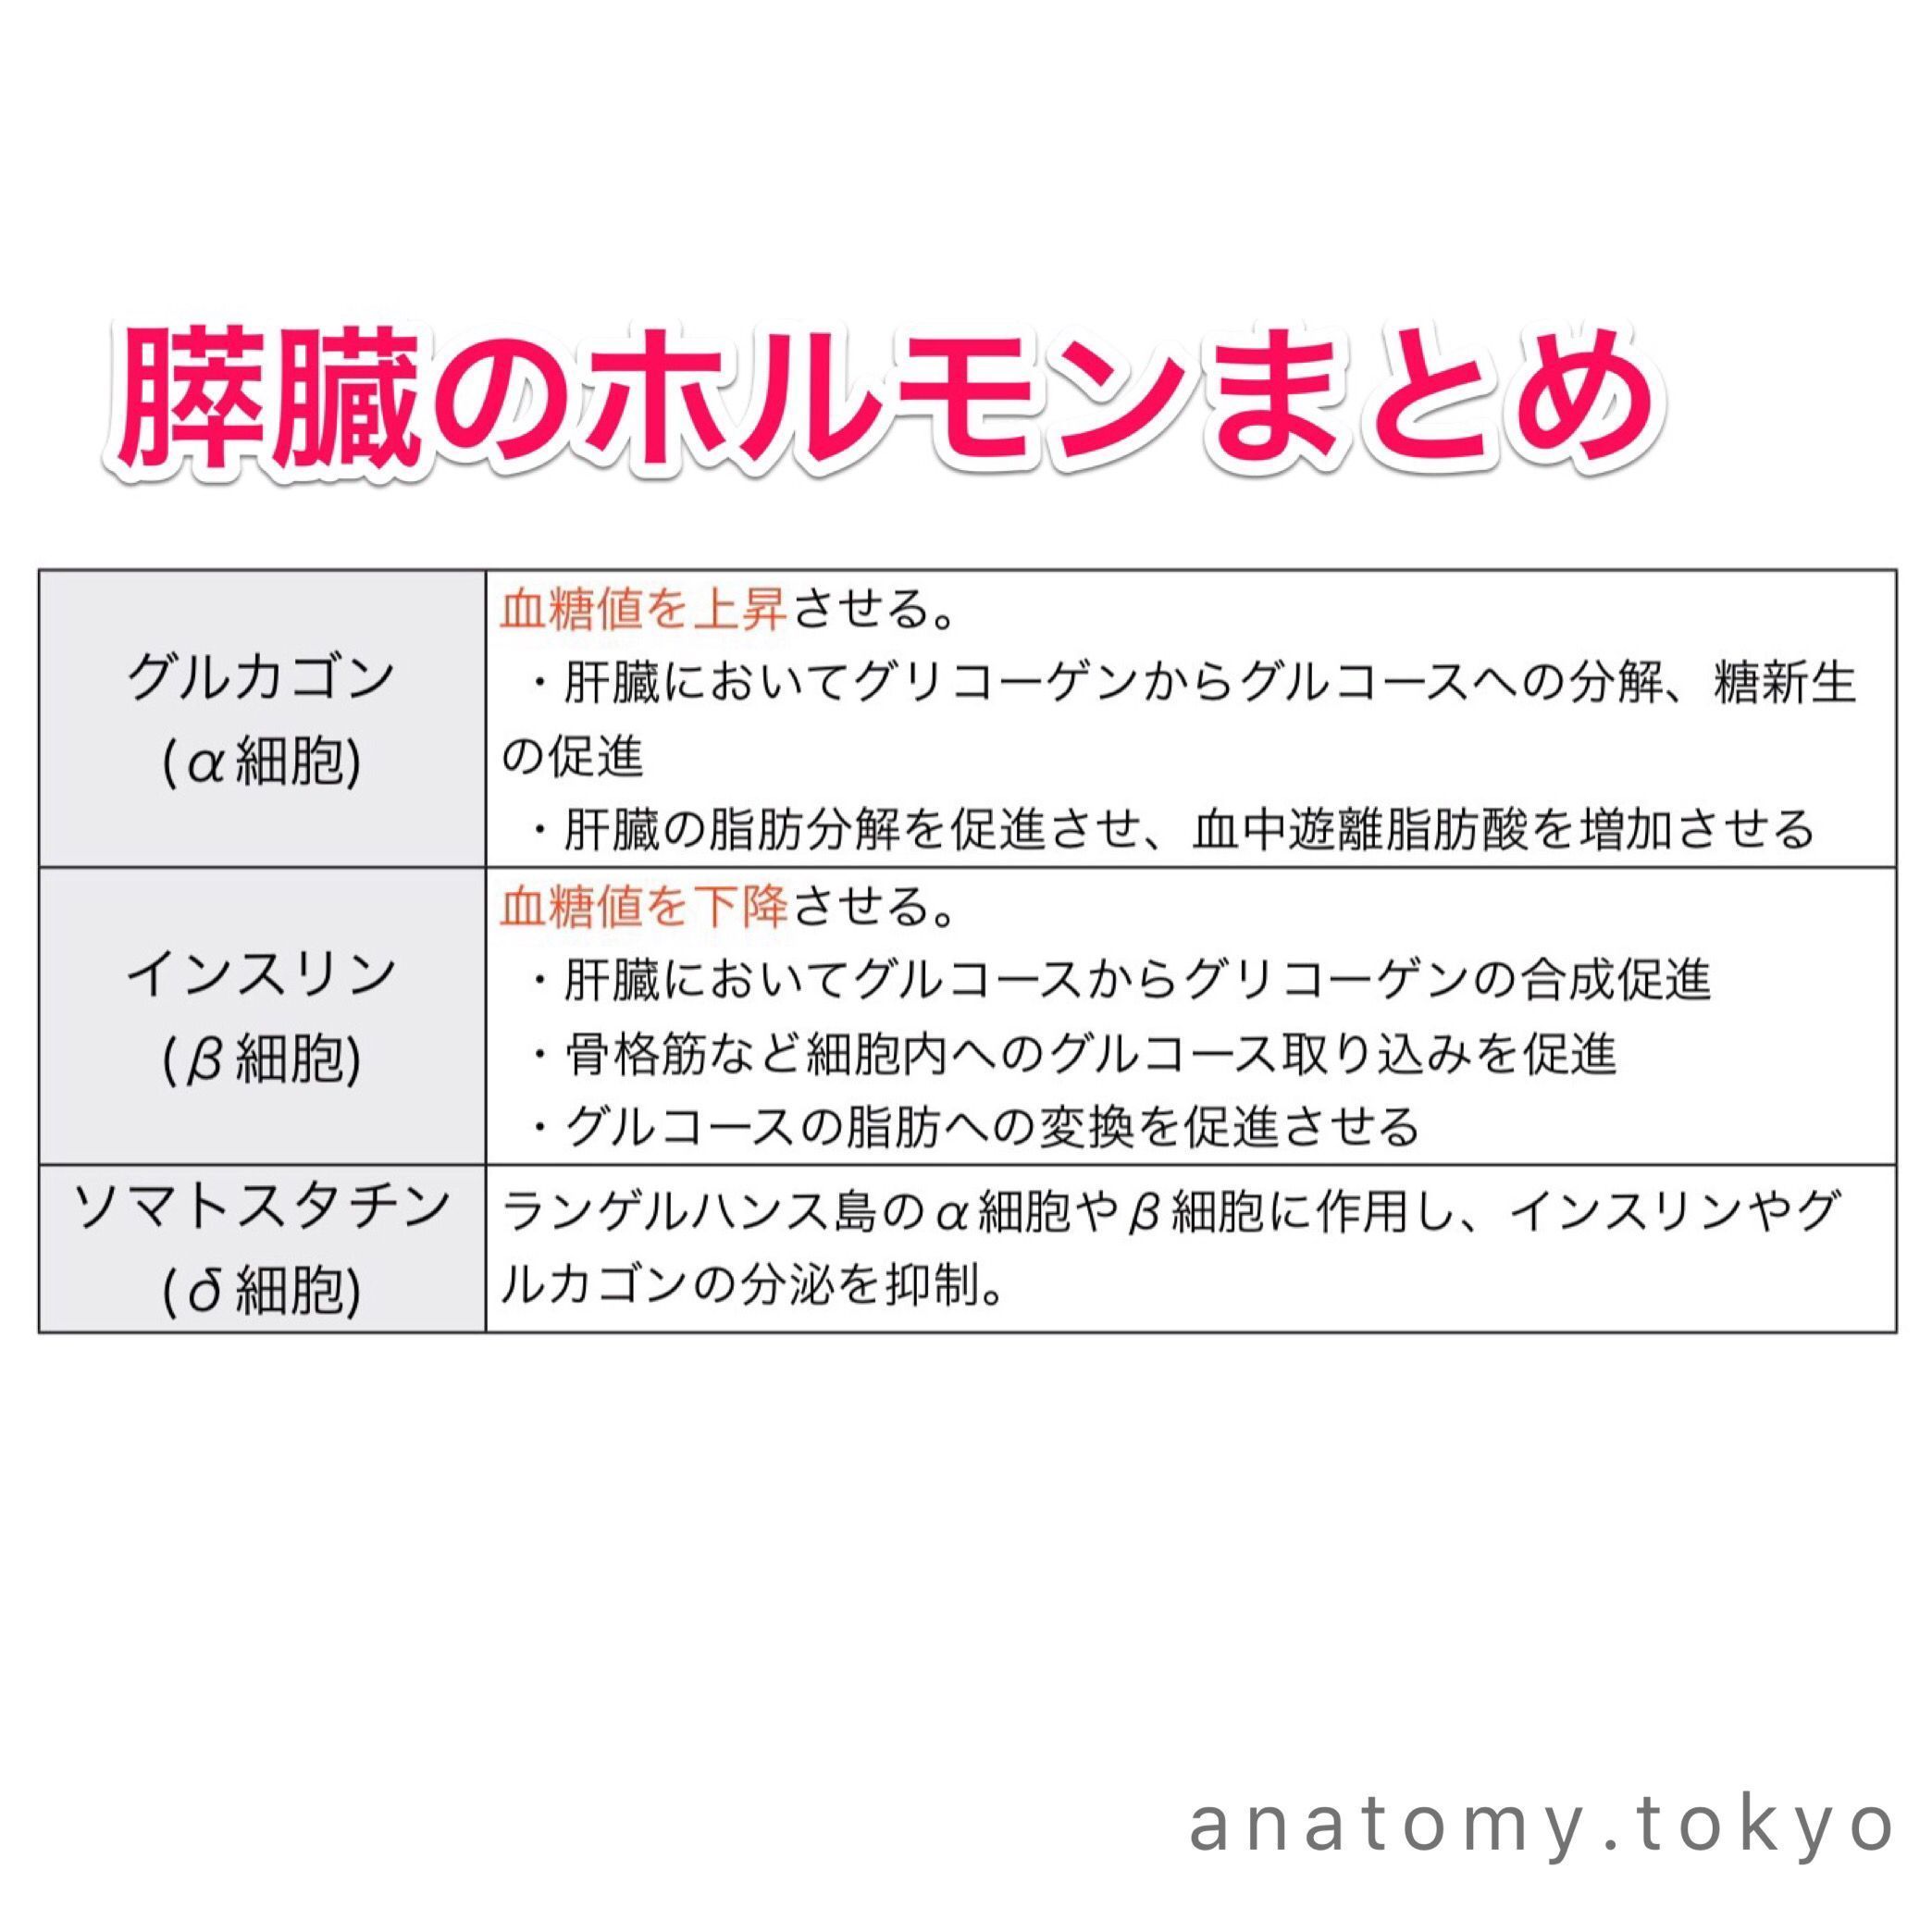

ランゲルハンス島のb細胞は を分泌する 解答 インスリン ランゲルハンス島のb細胞はインスリンを分泌します 解剖学 消化器系 膵臓 ランゲルハンス島 インスリン 一問一答 Https Www Anatomy Toky Beta Cell Pancreas Pancreatic

かずひろ先生 なるほど解剖学 A Twitter ランゲルハンス島のa細胞は を分泌する 解答 グルカゴン ランゲルハンス島のa細胞はグルカゴンを分泌します 解剖学 消化器系 膵臓 A細胞 グルカゴン 一問一答 Https T Co Icfewyeejg Https T Co Rkfq1hktho

𝑴𝒓 薬剤師 国家試験 On Twitter 正答 3 1 脳下垂体後葉から分泌 腎臓の集合管での水の再吸収を促進 2 視床下部から分泌 プロラクチンの分泌抑制 4 視床下部 ランゲルハンス島d細胞 小腸d細胞から分泌 インスリンやグルカゴン ガストリンの分泌

膵島の内分泌細胞は 種 存在する 解答 3種 膵島の内分泌細胞は3種存在します B細胞が最も多いことも重要です 解剖学 消化器系 膵臓 ランゲルハンス島 膵島 A細胞 B細胞 D細胞 一問一答 Https Www Anatomy Tokyo Oqo 看護ノート 消化器系 解答